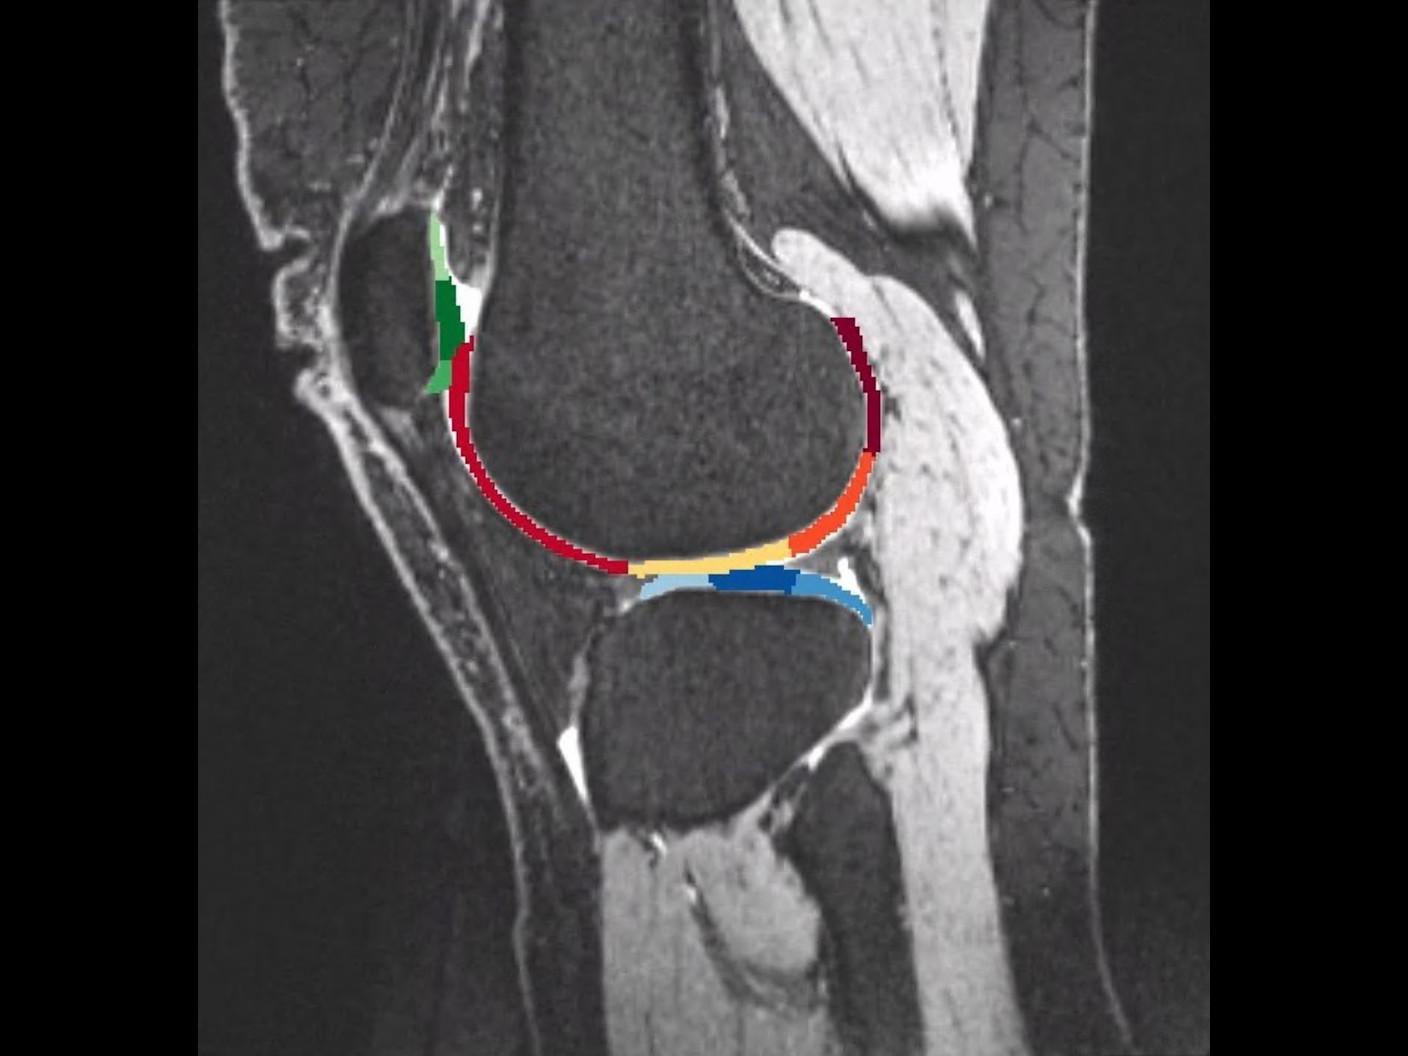

Now living back in Los Angeles, CA, USA, Joe has built a new life beyond the court even though pain is a constant companion, and frequent MRI scans are essential to guide his therapy. In the past, MRI exams were rather dreadful due to long waiting times, discomfort, and lengthy scans.聽

But everything changed when Joe experienced his first MRI scan at Eisenhower Imaging Center in Rango Mirage, CA, USA with the AI technology Deep Resolve. Discover in the video how Deep Resolve gives patients in pain not only clearer images but also hope.